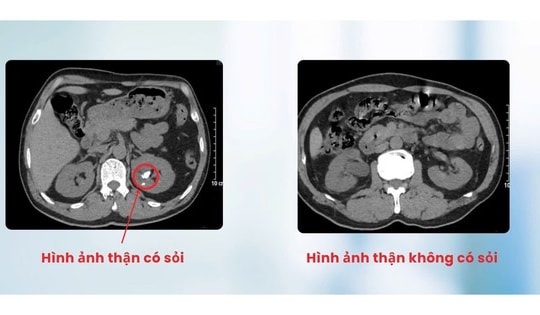

Tán sỏi qua da cho người đàn ông bị dị tật thận đôi cực hiếm

25/08/2025 08:41

Nhập viện trong tình trạng đau âm ỉ vùng thắt lưng trái, người đàn ông 60 tuổi ở Hải Phòng được phát hiện bị dị tật thận đôi cực hiếm, nhiều sỏi bên thận trái và được chỉ định tán sỏi qua da.